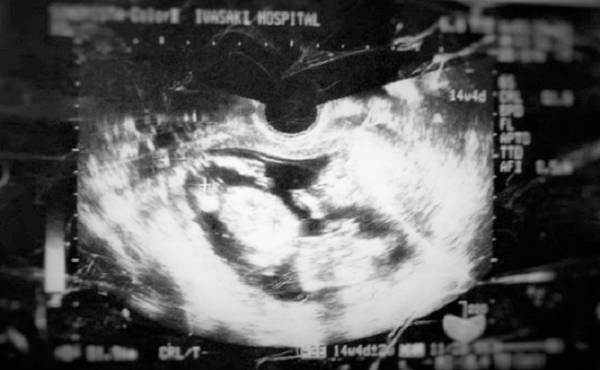

驚きの出生体重! 生まれた赤ちゃんは超ビッグだった【出産体験談】

第2子である次女の出生体重は、なんと4,268g! 生まれてびっくり!! とてもビッグな赤ちゃんでした。2度目の出産とはいえ、なかなか赤ちゃんが出てこなくて、分娩台の上でいろいろと悪戦苦闘! そのときのエピソードをご紹介したいと思います。

妊娠7カ月のときに微量の前期破水があり、子宮頚管を縛る手術をしていました。手術以降、医師より安静を言い渡されていたため、あまり動けなかったことが災いしてか、おなかの中の赤ちゃんの推定体重は今までにないほど増加の一途をたどりました。